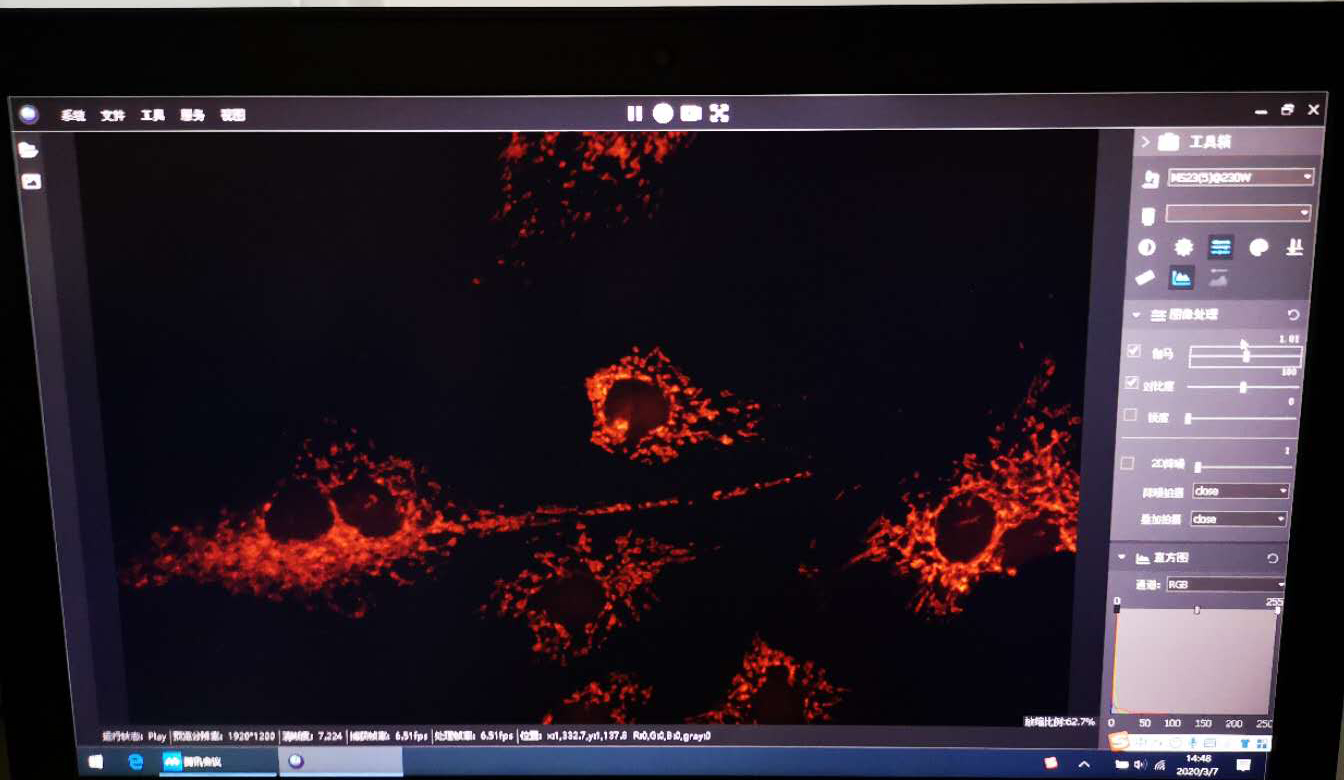

今年技術(shù)部同事給我們帶來了一場特別的產(chǎn)品培訓(xùn)(線上PPT+現(xiàn)場視頻演示);